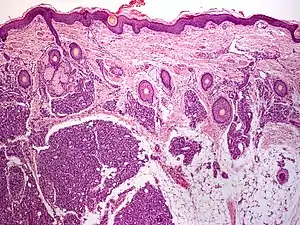

Tufted angioma

A tufted angioma (also known as an "Acquired tufted angioma," "Angioblastoma," "Angioblastoma of Nakagawa," "Hypertrophic hemangioma," "Progressive capillary hemangioma," and "Tufted hemangioma"[1][2]) usually develops in infancy or early childhood on the neck and upper trunk, and is an ill-defined, dull red macule with a mottled appearance, varying from 2 to 5 cm in diameter.[2]: 596